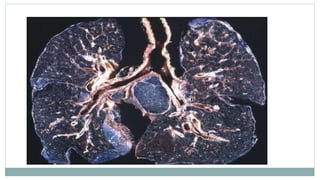

 Pathologically, silicosis is characterized by a dense

“nodular” fibrosis, the nodules ranging from 3 to 4 mm in

diameter.